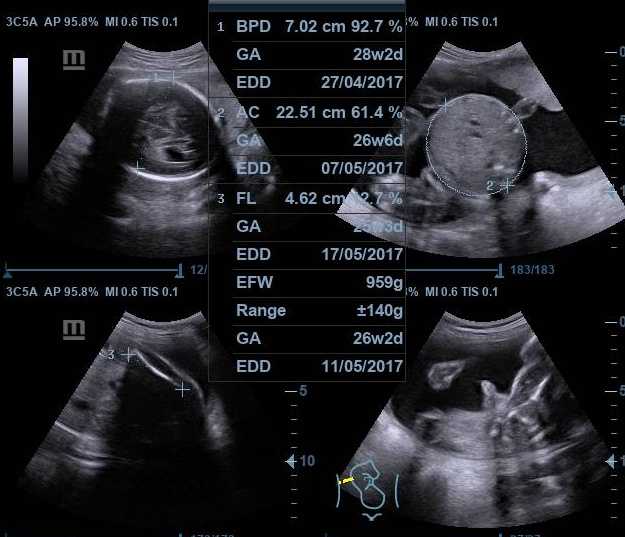

Usg Kedua Usg 2 Dimensi Di Rsud Hj Anna Lasmanah Banjarnegara Ceris Family

Usg Kedua Usg 2 Dimensi Di Rsud Hj Anna Lasmanah Banjarnegara Ceris Family

Dwitunggal Abadi Nusa On Twitter Contoh Hasil Usg 2 Dimensi Usg2d Usg2dimensi Usg Hasilusg Usgmindray Mindray Mindrayindonesia Healthcare Medical Dc70exp Dc70expert Dtamedika Https T Co Lwrm6xjjae

Dwitunggal Abadi Nusa On Twitter Contoh Hasil Usg 2 Dimensi Usg2d Usg2dimensi Usg Hasilusg Usgmindray Mindray Mindrayindonesia Healthcare Medical Dc70exp Dc70expert Dtamedika Https T Co Lwrm6xjjae

Dwitunggal Abadi Nusa On Twitter Contoh Hasil Usg 2 Dimensi Usg2d Usg2dimensi Usg Hasilusg Usgmindray Mindray Mindrayindonesia Healthcare Medical Dc70exp Dc70expert Dtamedika Https T Co Lwrm6xjjae

Dwitunggal Abadi Nusa On Twitter Contoh Hasil Usg 2 Dimensi Usg2d Usg2dimensi Usg Hasilusg Usgmindray Mindray Mindrayindonesia Healthcare Medical Dc70exp Dc70expert Dtamedika Https T Co Lwrm6xjjae

Dwitunggal Abadi Nusa On Twitter Contoh Hasil Usg 2 Dimensi Usg2d Usg2dimensi Usg Hasilusg Usgmindray Mindray Mindrayindonesia Healthcare Medical Dc70exp Dc70expert Dtamedika Https T Co Lwrm6xjjae

Dwitunggal Abadi Nusa On Twitter Contoh Hasil Usg 2 Dimensi Usg2d Usg2dimensi Usg Hasilusg Usgmindray Mindray Mindrayindonesia Healthcare Medical Dc70exp Dc70expert Dtamedika Https T Co Lwrm6xjjae